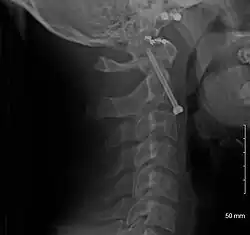

A fracture of the base of the dens as seen on plain X-ray

A fracture of the base of the dens as seen on CT